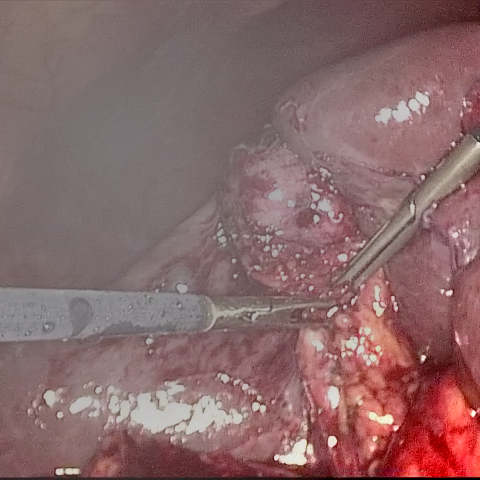

Refer to caption (a) Input Refer to caption (b) DIACMPN Refer to caption (c) Desmoke-LAP Refer to caption (d) PFAN Refer to caption (e) MITNET Refer to caption (f) Salazar Refer to caption (g) Dehamer Refer to caption (h) Ours Refer to caption (i) Target

Figure 3: Comparison of different methods on the LSD3K dataset.

IV-C2 Qualitative Analysis

Figures 3 and 2 provide a visual comparison of the desmoking results on challenging images from the test sets. The visual results corroborate our quantitative findings. DCP not only fails to remove the dense smoke but also introduces severe color distortion. CNN-based methods like FFA-Net and MSBDN successfully remove a large portion of the smoke but tend to either leave behind a thin layer of residual haze or over-smooth the image, losing critical textural details of the tissue and surgical instruments. The Transformer-based methods, DehazeFormer and PFAN, produce significantly better results by restoring more details. However, they can sometimes struggle with non-uniform smoke distribution, resulting in regions with unnatural brightness or minor artifacts.

In stark contrast, our RGA-Net generates visually superior results that are remarkably close to the ground-truth images. It effectively removes even the densest plumes of smoke while simultaneously preserving fine-grained details, such as blood vessels, tissue textures, and reflections on surgical tools. Furthermore, the color and illumination of the restored scene appear more natural and consistent, which is a direct benefit of our model’s ability to handle both local and global features through its hybrid attention and cross-gating mechanisms. This enhanced visual clarity is crucial for improving the surgeon-robot interface in real-world clinical applications.